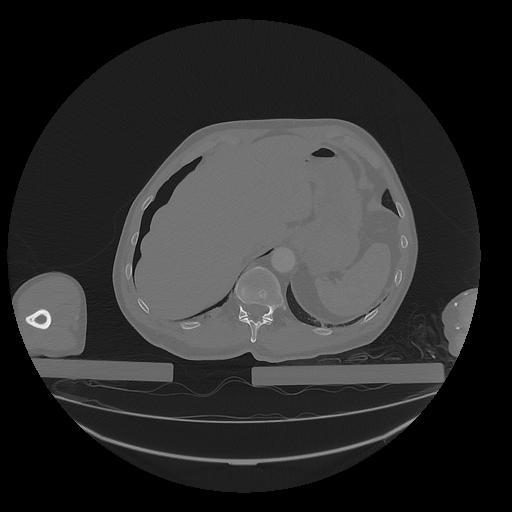

31 PULMON,CE,Vol,1.0,PULMON,,